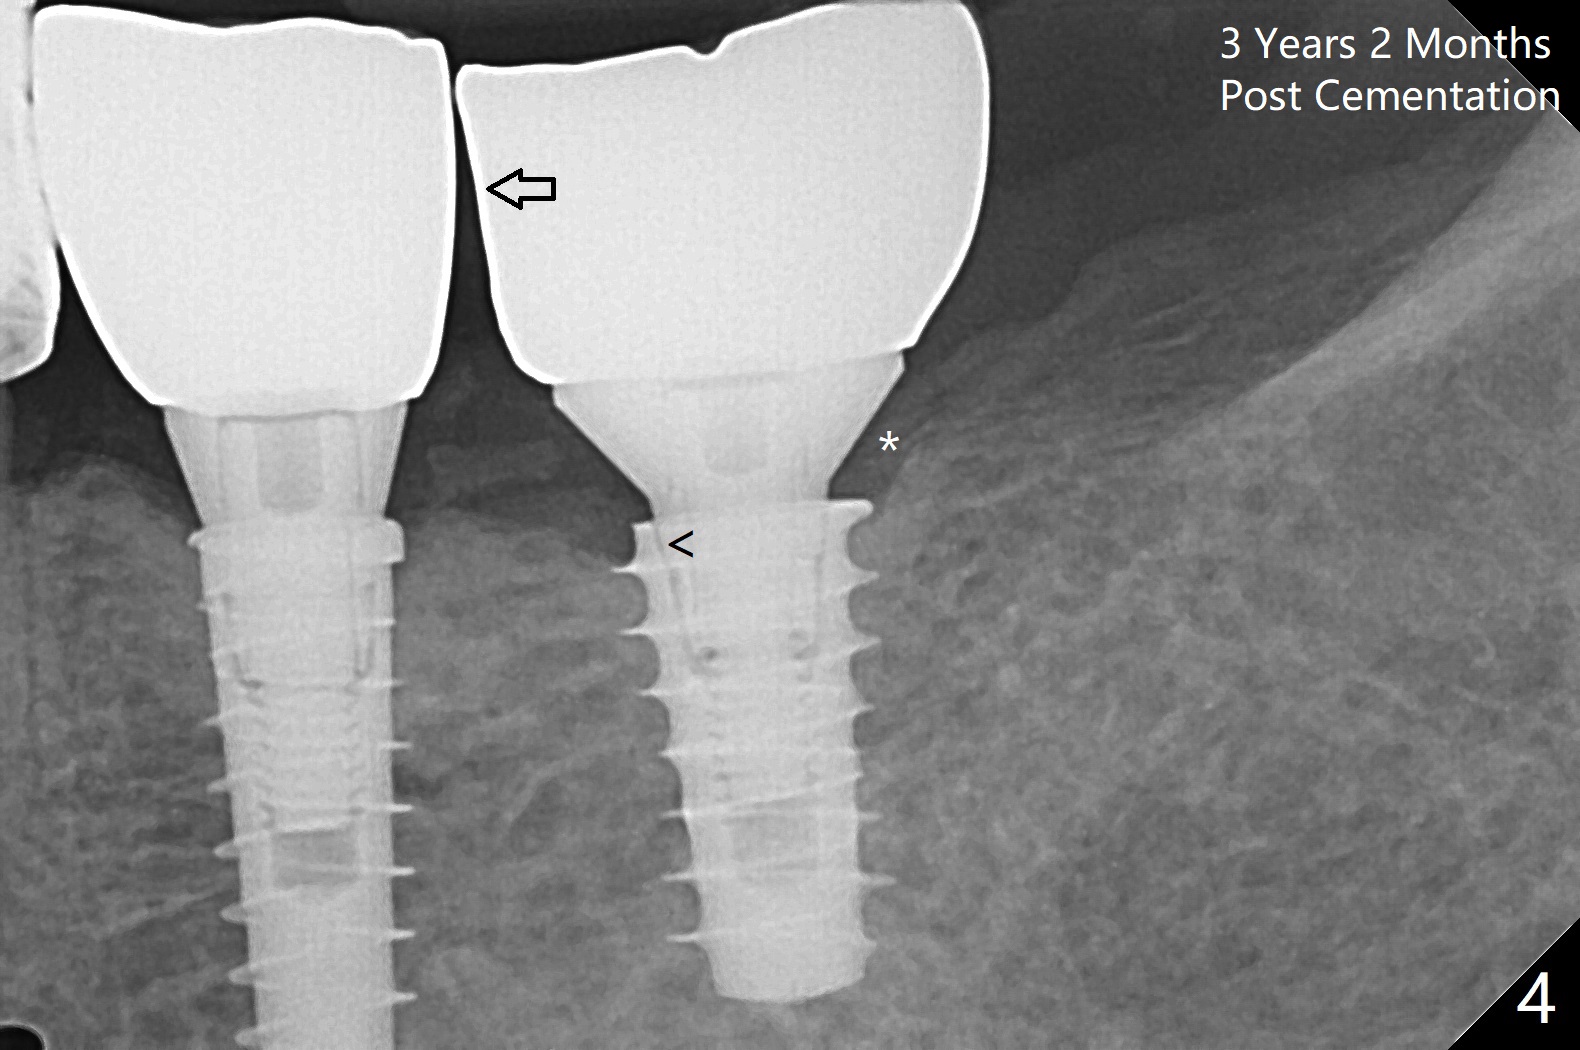

Because of the narrow ridge top at the sites of #19 and 18, it is reduced (Fig.1 arrowheads) prior to initial osteotomy with 1.6 mm pilot drill. After Magic Drills (3.3 and 4.3 mm at #19 and 18, respectively), 4x11 and 5x9 mm IBS implants are placed with insertion torque >35 Ncm with immediate placement of pair abutments (4.5x5.7(2) and 6.5x4(2) mm, Fig.2). In fact these sites are converted to a premolar and a 1st molar (because narrow ridge at #19). Following GBR and suturing, periodontal dressing is applied around the abutments for increased retention. The regional ridge reduction makes Marking Bur unnecessary (because of flat ridge top and the soft bone in this case) and more importantly there is no thread exposure upon implant placement. The trimmed site (concavity) is favorable for bone graft and membrane placement. One month postop, loose perio dressing is removed and replaced by a splinted nonfunctional provisional. The implant sites look normal nearly 3 months postop; there is no bone loss (Fig.3). Impression is taken. The crown/abutment at #18 is loose 3 years 2 months post cementation; when the crown/abutment is retightened, the abutment remains incompletely seated (Fig.4 <) in spite of reduction of the proximal contact (arrow). It may be due to the block of the distal crest (*). After use of 5.5 mm profile drill, the 6.5x4(2) mm abutment remains unseated (Fig.5). The smaller one (5x4(2) mm, Fig.6) is seated. When the redo crown is cemented, the surrounding gingiva is healthy with a short papilla between the implant crowns (Fig.7).